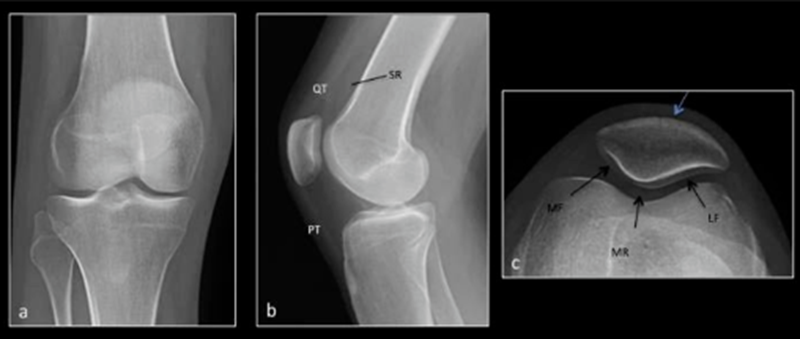

常见影像学检查包括X线、CT和MRI检查。X线早期无异常,直到晚期阶段,如出现广泛的软骨丧失、关节间隙丧失及相关的软骨下骨硬化和囊性变化,X线可诊断。MRI是非侵入性诊断方法,有望在肉眼可见的形态学软骨损失之前检测软骨病变以及软骨内部紊乱的独特功能。

正常X线 a.膝关节正位 b.膝关节侧位 c.髌骨轴位